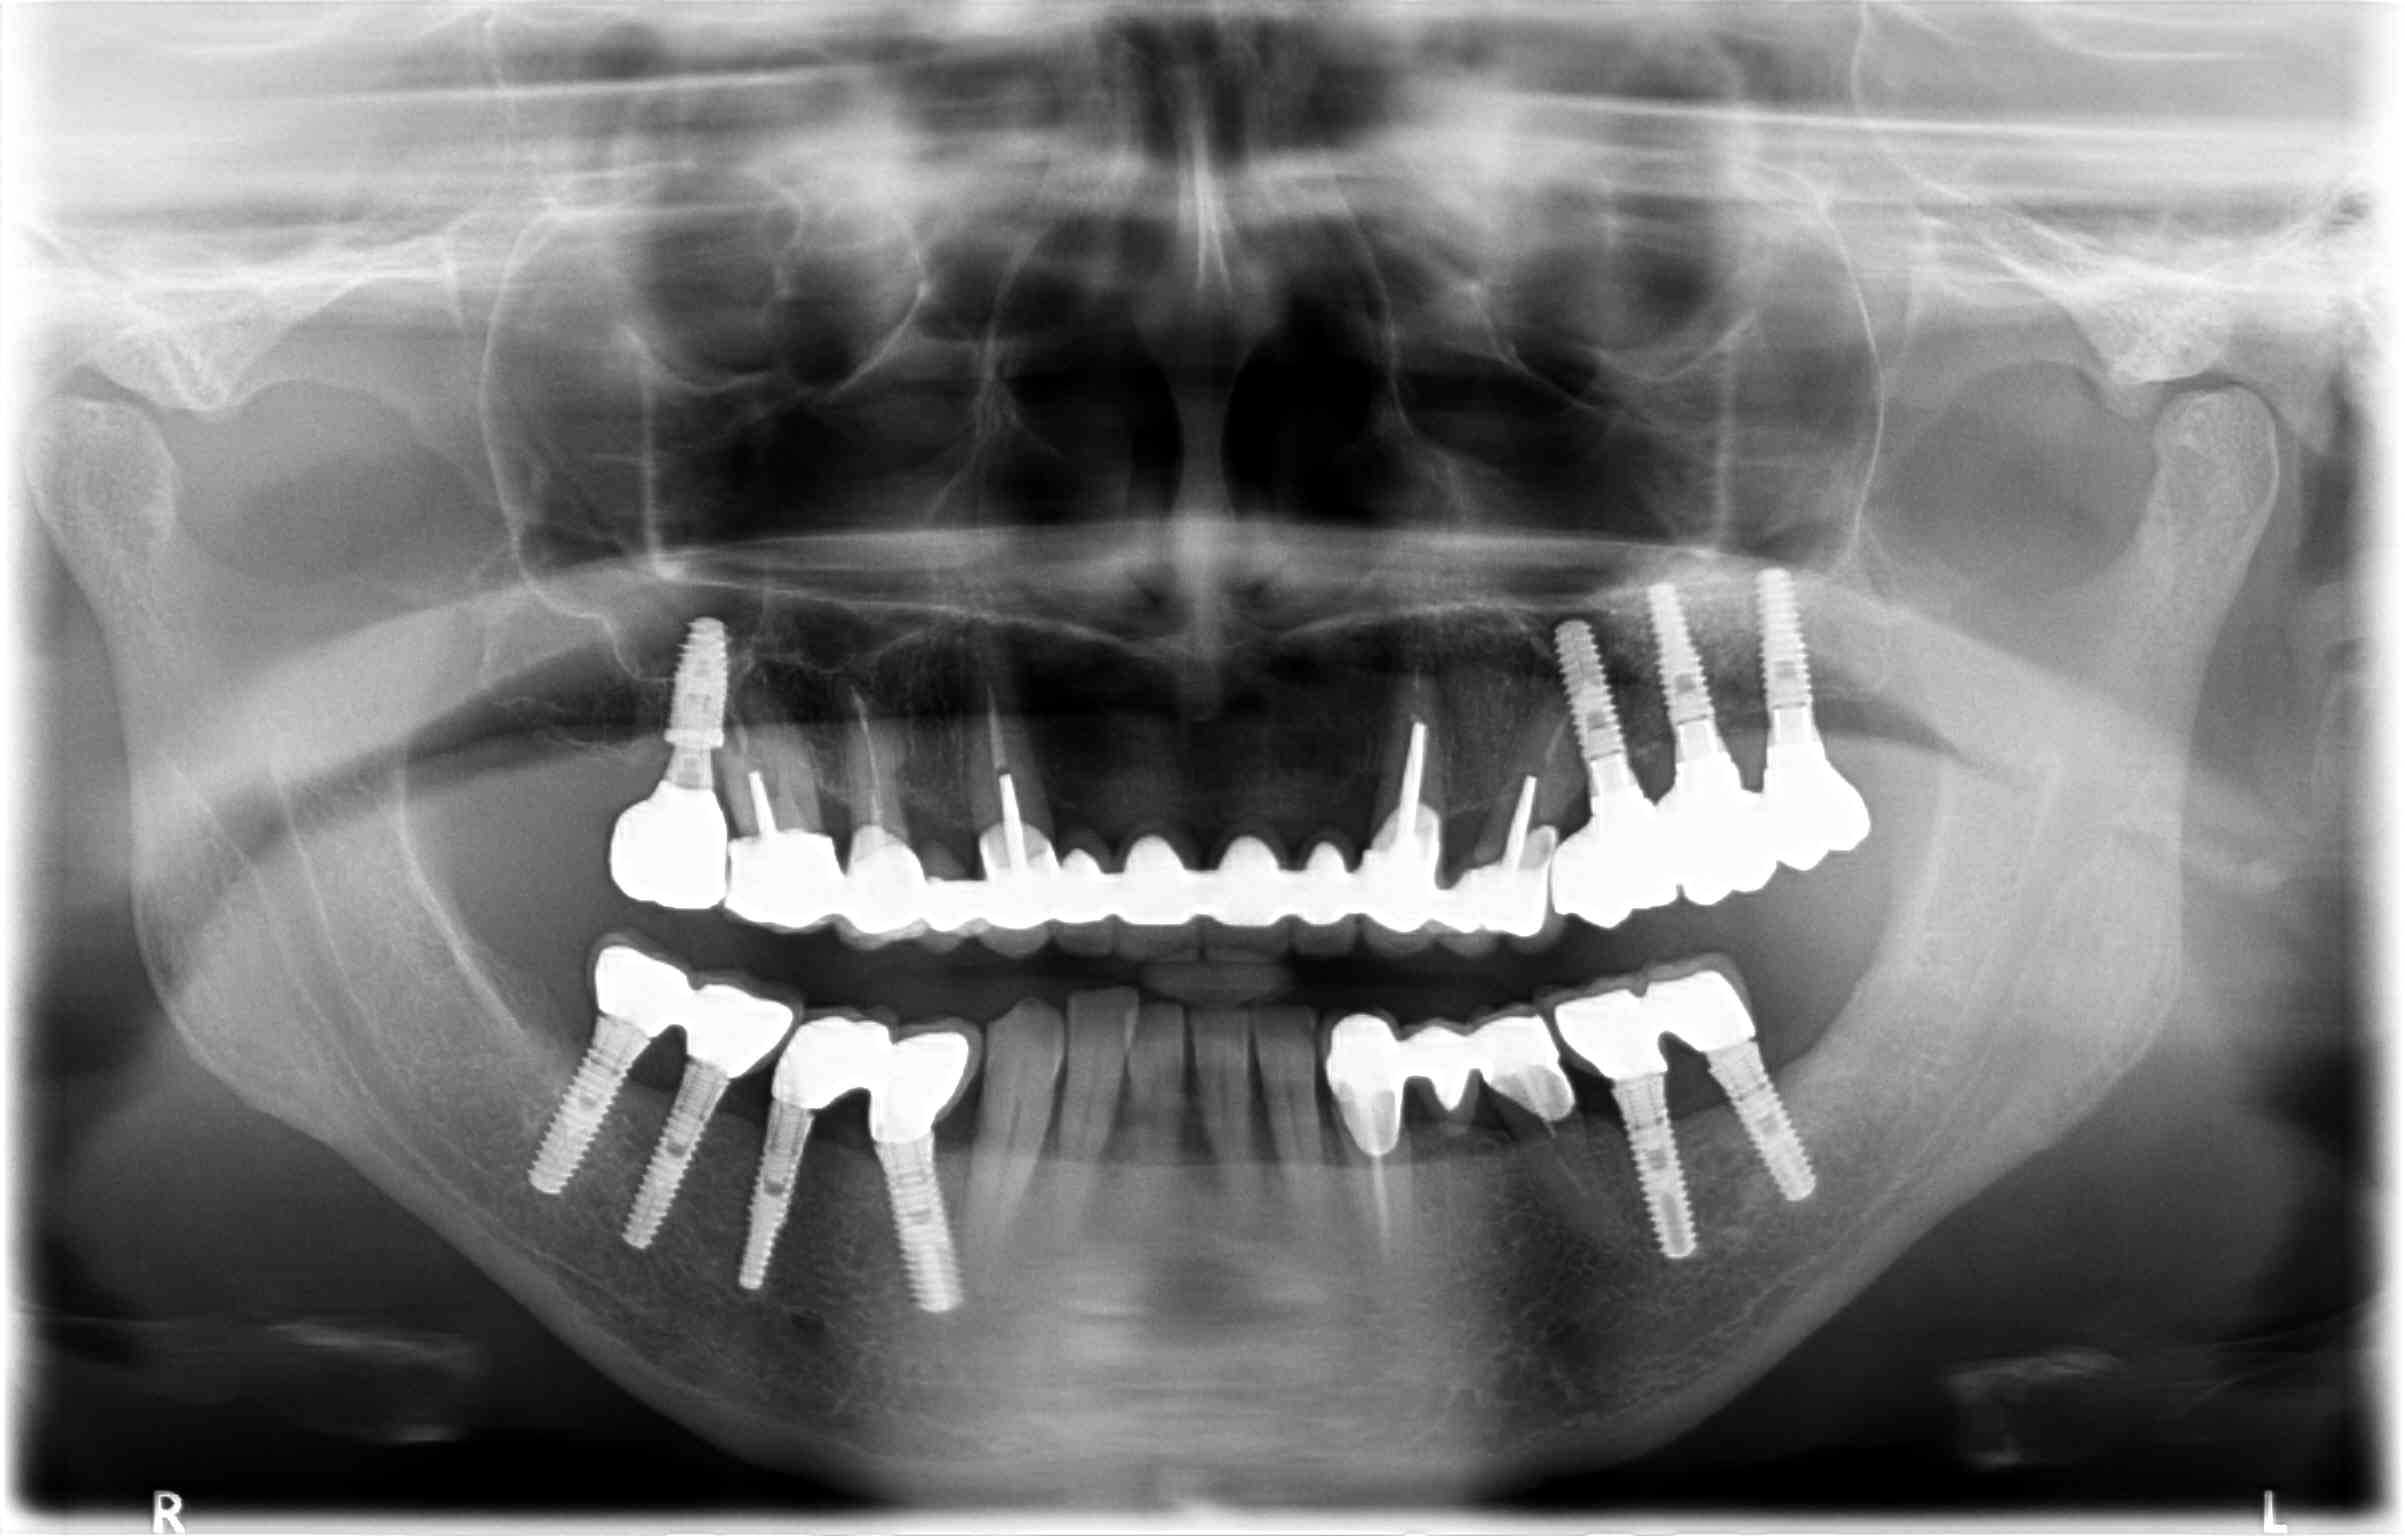

patiente qui vient avec bridge sup descellé au niveau de 23 et 24 mais bien fixé par ailleurs + reprise de carie sur 16. Que feriez vous ? La proximité des implants avec les dents naturelles m'ennuie, pour ne pas dire plus

L'axe de la 24 pas glop, le point de ctc 24/25 à créer... beaucoup de CR sur implants qui ont peut-être modifié les rapport occlusaux et généré un descellement... quand c'est plus étanche, souvent cela carie.

ç est quoi ? une classe 2 ? avec une arcade en forme de lyre ?

Ca gêne personne les couronnes sur implant en bas à gauche (et un peu à droite) pas enfoncées à fond ?

J'avoue les couronnes sur implants en bas m'interpellent un peu aussi... Quand au haut, je dirai tant que tu n'as pas démonté impossible à dire.

ton bridge a 10 ans ? mais combien ont les implants autour, car les couronnes sur implants on pu modifier une bonne occlusion et créer un déséquilibre qui explique ce descellement aussi.